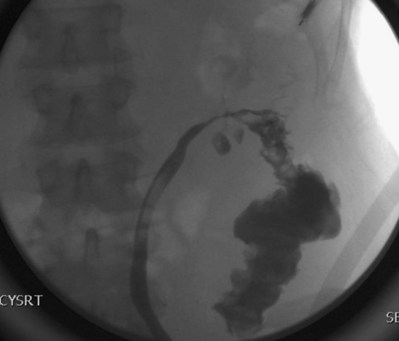

A cystogram and/or voiding cystourethrogram (VCUG) and an upper tract study should be performed in patients being evaluated for a VVF. The cystogram may objectively determine the presence and location of the fistula. Upon filling of the bladder, contrast often begins to opacify the vagina, almost immediately confirming the presence of a VVF. VVF are often best seen in the lateral projection (Fig. 77–7) in which the bladder and vagina are not superimposed. Often, the actual VVF tract may be visible in the lateral projection (Fig. 77–8). However, voiding images may be necessary in some patients with small fistulae, to demonstrate the VVF. The slight increase in intravesical pressure that accompanies micturition is usually adequate to demonstrate even very small fistulae. Importantly, a cystogram that fails to demonstrate a suspected VVF, but lacks voiding images or postvoid images, should be considered nondiagnostic. During voiding, care should be taken to exclude vaginal voiding or reflux of contrast from the introital region cephalad into the vagina, which would produce a falsely positive image. An involuntary bladder contraction can be provoked with rapid filling during cystography, and if the intravesical pressure rises sufficiently, this may also be sufficient to demonstrate a VVF when the filling images of the cystogram failed to demonstrate it. In some instances, a cystogram can also make an assessment of bladder capacity (important in the setting of prior radiotherapy), cystocele, bladder neck competence, and vesicoureteral reflux, any of which may have an impact on operative repair.

Figure 77–7 Cystogram demonstrating a vesicovaginal fistula (VVF). A, Lateral image demonstrates a posthysterectomy VVF. B, Anteroposterior view. The contrast agent is seen opacifying and outlining the vagina superimposed on the bladder.